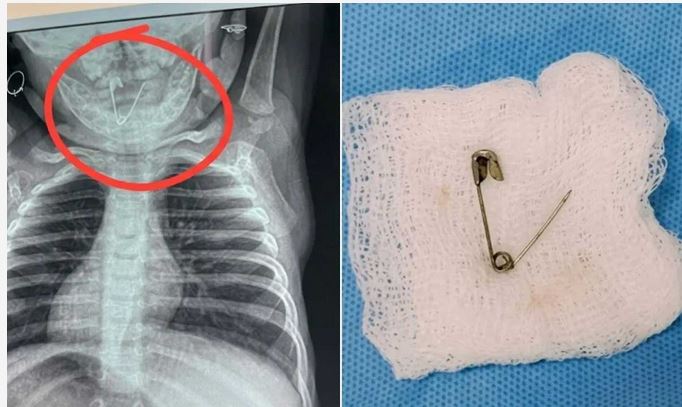

डॉक्टरों की सलाह पर बच्चे का एक्स-रे कराया गया। रिपोर्ट देखते ही मेडिकल टीम के होश उड़ गए, क्योंकि बच्चे के गले में एक खुली हुई सेफ्टी पिन फंसी हुई थी। यह स्थिति बेहद खतरनाक थी, क्योंकि पिन किसी भी समय अंदर खिसककर जानलेवा साबित हो सकती थी।

डॉक्टरों ने तुरंत रत्नागिरी के नवजात का ऑपरेशन करने का निर्णय लिया, लेकिन सर्जरी शुरू होने से पहले ही स्थिति और गंभीर हो गई। सेफ्टी पिन गले से फिसलकर भोजन नली (इसोफेगस) में पहुंच गई। इससे जोखिम कई गुना बढ़ गया और जरा सी चूक भी बच्चे के लिए घातक साबित हो सकती थी।

इस नाजुक परिस्थिति में ईएनटी विशेषज्ञों ने सूझबूझ दिखाते हुए एसोफैगोस्कोपी तकनीक का सहारा लिया। इस प्रक्रिया के जरिए बेहद सावधानीपूर्वक पिन को बाहर निकाला गया। ऑपरेशन के दौरान हर पल चुनौतीपूर्ण था, लेकिन डॉक्टरों ने धैर्य और सटीकता के साथ इसे सफल बनाया।